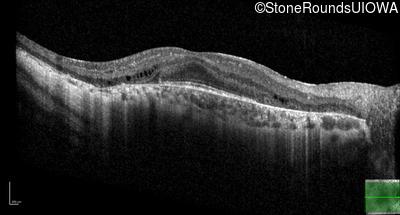

Optical Coherence Tomography - Right - 20/25 +1

Exemplar / OCT Stack